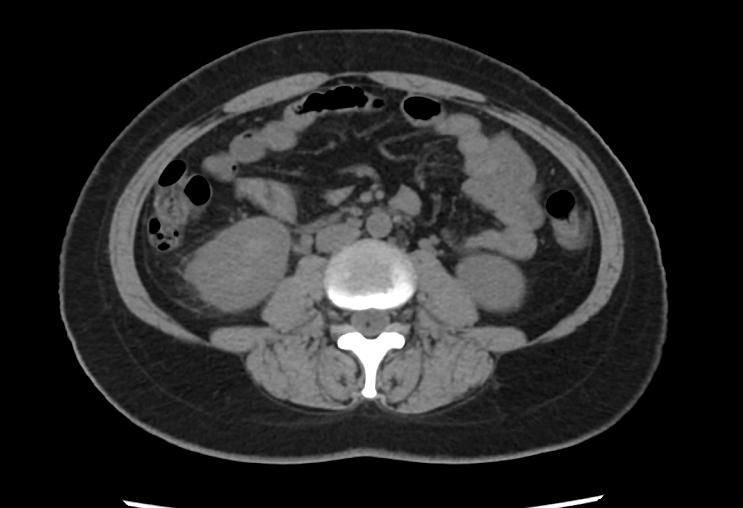

赵女士是因为右侧腰痛伴发热来门诊就诊的,这两天发热最高达39摄氏度。同时伴有尿频尿急尿痛等膀胱刺激症状。我给赵女士做了体格检查,右侧肾区叩击痛明显。从赵女士的症状和体征来看,是比较符合急性肾盂肾炎的。为了进一步明确诊断,我给她化验了尿常规、尿培养以及血常规、C反应蛋白和降钙素原等感染指标,结果显示尿和血白细胞都明显升高,感染指标也是高的,尿培养显示大肠杆菌感染,同时我们也给赵女士完善了尿路CT,显示右侧肾脏周围有比较明显的炎性渗出,符合肾盂肾炎的影像学表现。

图一:腹部CT显示右侧肾脏周围渗出明显